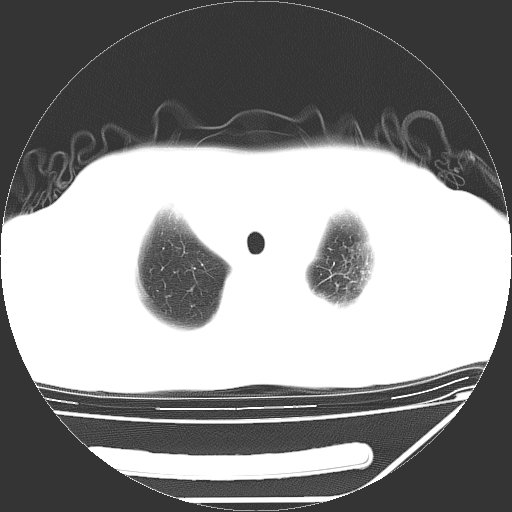

男,13岁,咳嗽、咳痰伴发热一周。

中上纵隔见多枚淋巴结肿大,部分相互融合成团片,左肺门增大,上叶支气管变窄,肺内多处斑片状 索条状及棉絮状致密影。临床“男,13岁,咳嗽、咳痰伴发热一周。”首先考虑:原发综合征!不除外淋巴瘤可能!

纵隔多发肿大淋巴结,部份有融合改变。双肺血管气管束增厚,以肺门为中心向外周散发,以左肺下叶为明显。考虑淋巴瘤可能性大。不除外原发综合征。

单纯看片子感觉左侧肺通气不畅,而不像肺内病变引起的纵隔病变。而且纵隔及左肺门都有淋巴结增大。首先还是考虑一下结节病,不排除淋巴瘤!!!